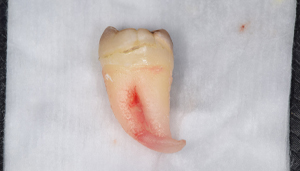

右下の親知らずが疼く症例

- 抜歯前写真(レントゲン)

- 抜去歯の写真(CT画像)

| 年齢 | 30代・女性 |

|---|---|

| 主訴 | 右下親知らずが疼く |

| 親知らずの生え方 | 横向きに生えている |

| 抜歯時間 | 40分 |

| 費用 | 約8,000円(保険診療、CT代含む) |

| 抜歯内容 | 右下の親知らずは横向きに生えて埋まっているため、麻酔をし親知らずの奥に切開を入れて歯ぐきを開き、歯を囲んでいる骨を削り歯の頭部分を割って出してから、残った根の部分を取り出して抜歯は終了しました。 歯ぐきを切った部分は糸で縫っています。このケースでは根の先端が神経に近く麻痺のリスクがありましたが事前にCTを撮影し、神経との位置関係を確認していたため、麻痺が残ることはありませんでした。 約1週間後に糸取りを行い、その際も多少の痛みや腫れはありましたが後日その痛みも無くなりました。 |